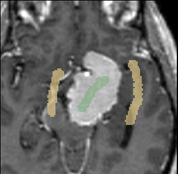

After the segmentation, the user can edit the segmentation by providing additional gestures in the image as illustrated in the figure below.

Additional edits added to the existing segmentation

Final segmentation

The segmentation resulting from the user's edit is also shown.